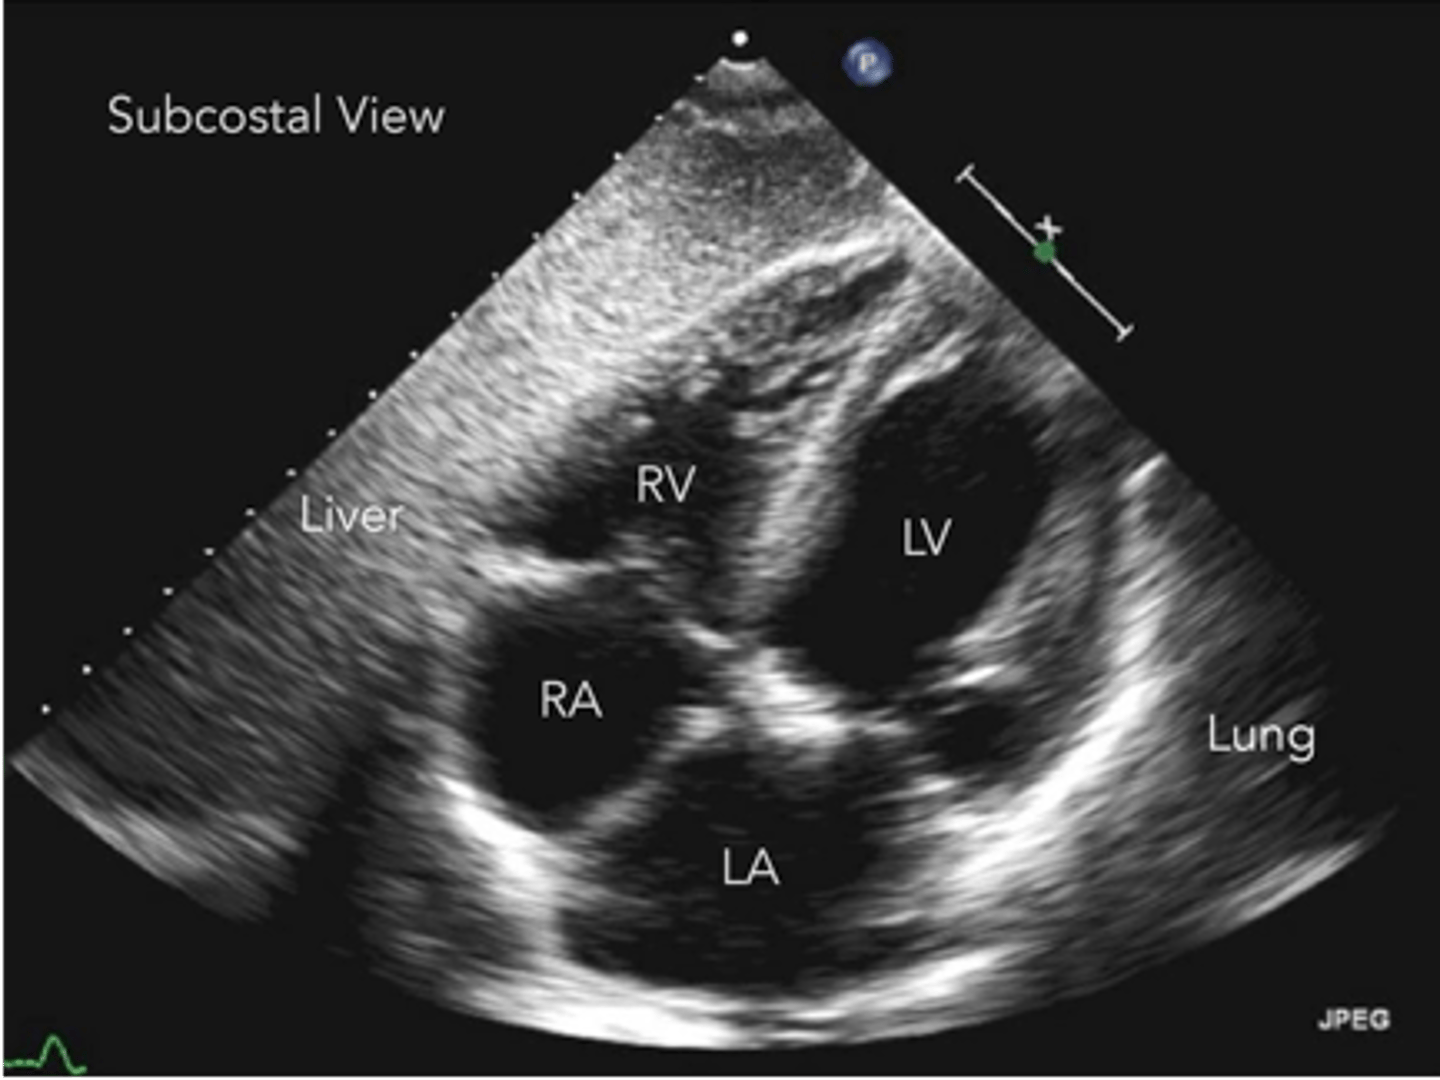

anterior tricuspid valve leaflet

left leaflet

septal/medial tricuspid valve leaflet

right leaflet

anterior tricuspid valve leaflet

left leaflet

medial/septal tricuspid valve leaflet

right leaflet

anterior tricuspid valve leaflet

top leaflet

septal/medial tricuspid valve leaflet

bottom leaflet